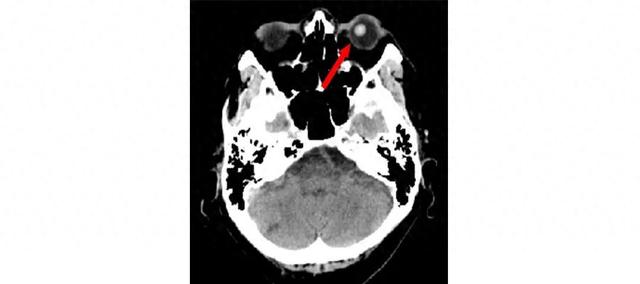

患者,男。70岁、既往健康,在观看电视时,左眼突然失去视力,并伴随从左眼延伸至头部左侧的剧烈疼痛。由于疼痛难以忍受,患者无法自行睁开左眼,导致直接进行眼部检查困难。这种突发头痛与视力丧失症状,不仅提示了青光眼急性发作的可能性,也可能存在颅内病变的风险。为了排除诸如蛛网膜下腔出血等严重颅内疾病,急诊头部CT检查。CT结果显示,患者的左人工晶状体位置异常,向后倾斜(见图)。基于这一发现,患者被紧急转诊至眼科进一步诊治。在眼科,经过详细评估后,确诊为因晶状体脱位导致的急性青光眼发作。随后,该患者接受了左侧玻璃体切割手术。

对于本例患者,自发晶状体脱位是在没有明显触发因素的情况下发生的;房水通道阻塞导致继发性闭角型青光眼。晶状体脱位最常见的原因是外伤。没有易感遗传因素的自发晶状体脱位很少见。头部CT有助于诊断伴有眼部疼痛的突然视力丧失患者的晶状体脱位。